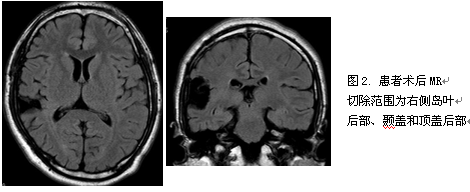

科内讨论后结果:考虑为岛叶癫痫可能性大,以岛叶后部为重点,以左侧为著,需要立体定向脑电图(SEEG)植入,电极主要覆盖左侧岛叶、顶盖、颞盖,右侧岛叶少量电极以鉴别侧向性。SEEG共记录13次发作,发作症状学同前, 发作期脑电图提示右侧L’9-11电极驻点(颞上回后部-颞横回-岛后长回)放电迅速扩散至左侧对称的L电极(颞上回后部-颞横回-岛后长回),引起右侧的强直-阵挛发作。手术切除右侧岛叶后部、颞盖和顶盖后部,术后病理:符合局灶性皮质发育不良(Ib)。患者术后至今1年半无发作。

患者发作期症状学为右侧的强直阵挛,提示左侧大脑半球起始,似乎致痫灶定侧是有把握的。但定位存在困难,需要SEEG植入。因考虑到可能为岛叶的发作,而岛叶发作可能很快扩散到对侧,给予双侧岛叶的植入,但以左侧为主,右侧少量电极以鉴别。SEEG提示患者发作起始于右侧半球,与之前的预判有出入。为进一步明确右侧情况,在右侧进行了电极的补充植入,成功发现右侧岛叶后部、颞盖和顶盖的致痫灶,手术切除后至今未再出现发作。